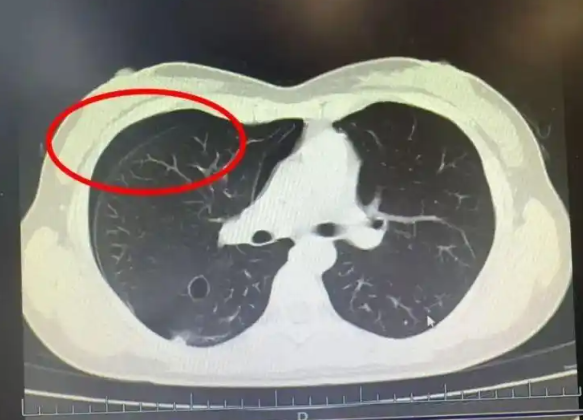

據《紅星新聞》報導,何醫師看了王小姐的胸部CT後表示,患者是自發性氣胸,也就是俗話說的爆肺,便收治入院進行胸腔穿刺抽氣,「所幸置管引流後,住院5天就好轉出院了。」

▲何醫師指出,王小姐的胸部CT顯示,是自發性氣胸。(圖/翻攝自紅星新聞)

何醫師指出,因為王小姐長期劇烈運動,使肺部壓力瞬間增大,導致肺泡破裂,氣體洩漏進胸腔,壓迫肺部,進而引發氣胸,「一般情況下,少量氣胸且無症狀者,可自然吸收,觀察即可,但如果不引起重視易嚴重會危及生命,麻煩就大了。」